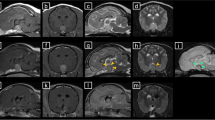

Incubation with 50 nM ACTH(1–24) significantly (P < 0.01 or lower) upregulated the mRNA expression of all the genes analyzed in this study, but most notably that of CYP17, followed by MRAP, CYP11B1 and StAR (Fig. 2). Co-incubation with 5 μM #776 significantly inhibited the ACTH-stimulated expression of five of the eight genes analyzed in this study (Fig. 2), while co-incubation with 5 μM #299 significantly inhibited the ACTH-stimulated expression of all the genes analyzed in this study (Fig. 2).

The effects of incubation with 50 nM ACTH(1–24) and of co-incubation of ACTH(1–24) with 5 μM of compounds BIM-22776 (#776) and BIM-22A299 (#299) on the relative mRNA expression of steroidogenic enzymes, MC2R, and MRAP in canine primary adrenocortical cell cultures (n = 8). Fold changes are normalized to the non-ACTH-stimulated controls, i.e. the basal expression. Asterisks represent significant differences: *P < 0.05, **P < 0.01, ***P < 0.001. All conditions were significantly different from the basal expression, except when indicated with an “a”. StAR, steroidogenic acute regulatory protein; CYP11A1, cytochrome P450 side chain cleavage; CYP17, 17α-hydroxylase/17,20-lyase; HSD3B2, 3β-hydroxysteroid hydrogenase type 2; CYP21, 21-hydroxylase; CYP11B1, 11β-hydroxylase cytochrome P450; MC2R, melanocortin 2 receptor; MRAP, melanocortin type 2 accessory protein